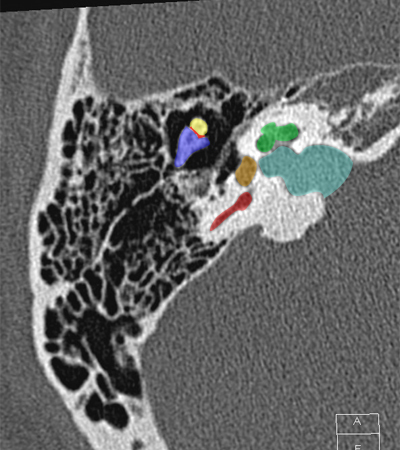

Radioanatomie du rocher sur coupes TDM

Différentes coupes de référence (A. Attyé 2013)

Coupe axiale passant par le canal semi-circulaire supérieur Coupe axiale passant par le canal semi-circulaire latéral Coupe axiale passant par le modiolus de la cochlée Coupe axiale passant par la fenêtre ronde Coupe axiale passant par le ganglion géniculé Coupe axiale passant par l'articulation incudo-malléaire Coupe axiale passant par la partie pétreuse de l'artère carotide interne Coupe axiale passant par le nerf tympanique

Coupe axiale passant par le foramen styloïde Coupe coronale passant par le muscle tenseur du tympan Coupe coronale passant par le recessus epitympanique Coupe sagittale passant par le segment mastoïdien du nerf facial coupe sagitalle oblique passant par le canal semi-circulaire supérieur (plan de Pöschl) Reconstruction axiale passant par le plan de l'étrier Coupe axiale passant par les apex pétreux